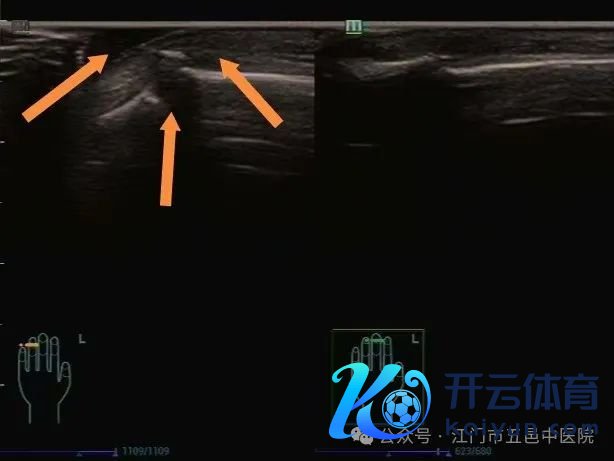

近日,小帅害怕不安地来到江门市五邑中病院畅通医学科就诊,科室大夫安排他进行了肌骨超声稽察,阐发教导其“右侧肱二头肌长头腱饱胀断裂”!

▲举杠铃引起的肱二头肌长头腱饱胀性断裂